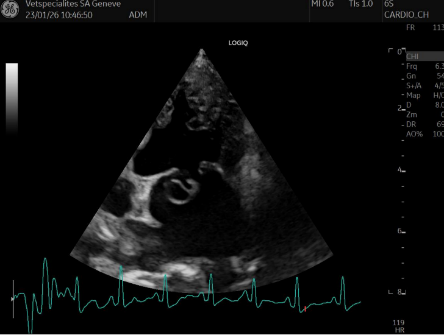

Les signes de la maladie mitrale sont visibles à l’échocardiographie, mais n’engendre aucun remodelage du cœur (seules les valves sont modifiées)

Les modifications des valves mitrales sont visibles à l’échocardiographie ET des signes de remodelage du cœur sont présents. Aucun symptôme clinique n’est encore présent

Différents stades de maladie myxomateuse mitrale ( Photo 1 : valve mitrale normale ; Photo 2 : prolapsus modéré, Photo 3 : prolapsus sévère)